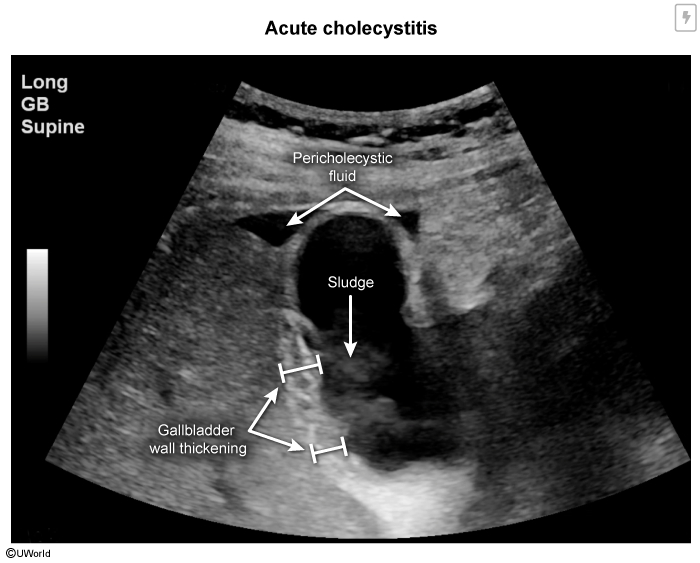

• Ultrasound (first-line):

• Gallbladder wall thickening >4 mm (most specific)

• Pericholecystic fluid

• Gallstones or sludge

• Sonographic Murphy's sign

• Gallbladder distension

• Sensitivity: 81%, Specificity: 83%